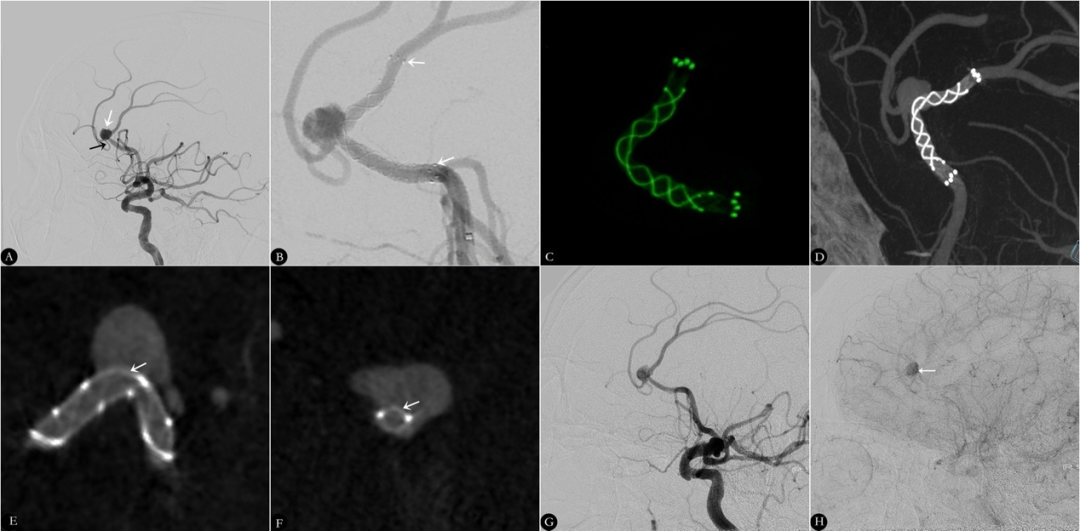

图1.FRED Jr治疗左侧大脑前动脉远端动脉瘤

A.3D-DSA提示左侧大脑前动脉A2段动脉瘤,大小2.4×2.7mm,瘤颈2.1mm,头颈比1.10,载瘤动脉远端和近端直径分别为2.7mm和3.1mm。B.术后影像学显示动脉瘤即刻对比剂明显滞留(白色箭头显示支架的头部和尾部)。C.HR-FDCT显示支架完全释放并完全贴壁(白色箭头示瘤颈处支架编织丝);D、E.动脉瘤颈处HR-DCT成像显示支架完全贴壁。F.6个月DSA下复查载瘤动脉通畅,动脉瘤完全闭塞。

图2.FRED Jr治疗左侧大脑前动脉远端动脉瘤

A.2D-DSA和提示左侧大脑前动脉A2段动脉瘤,大小5.3×7.1mm,瘤颈4.7mm,头颈比1.51,载瘤动脉远端和近端直径分别为2.6mm和3.2mm(白色粗箭头示动脉瘤,黑色细箭头示动脉瘤穿支动脉)。B.术后影像学显示动脉瘤即刻对比剂明显滞留(白色箭头显示支架的头部和尾部)。C、D.HR-FDCT显示支架完全释放并完全贴壁;E、F.动脉瘤颈处HR-DCT成像显示支架完全贴壁(白色箭头示瘤颈处支架编织丝)。G、H.6个月DSA下复查载瘤动脉通畅,动脉瘤延迟闭塞,但可见静脉期动脉瘤内造影剂滞留。